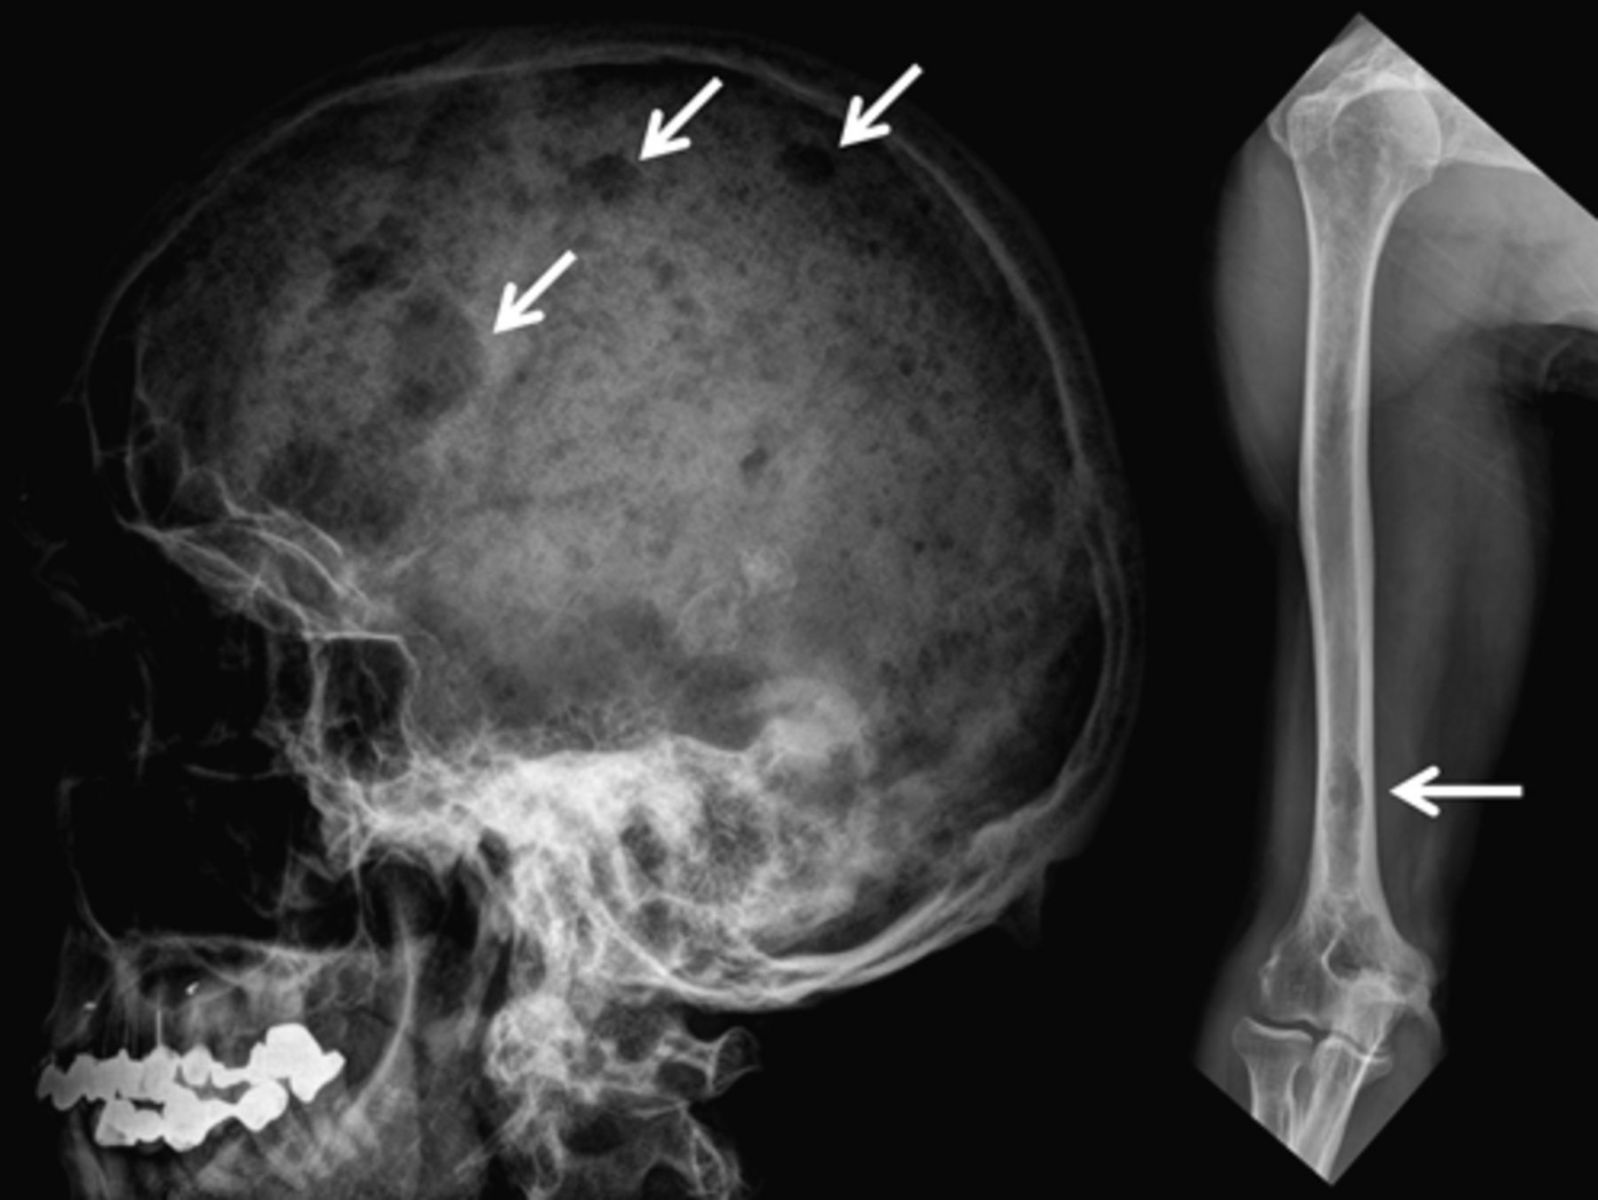

Остеолитические очаги округлой или неправильной формы без периостальной реакции, преимущественно в телах позвонков, рёбрах, черепе, тазовых костях и проксимальных отделах бедренных костей.

Нарушение симметрии и целостности крыши черепа и основания в виде участков просветления с чёткими краями.

- Определение точного количества, локализации и размеров остеолитических очагов до 2–3 мм.

- Высокая пространственная разрешающая способность при исследовании сводов черепа, рёбер и тазовых костей.